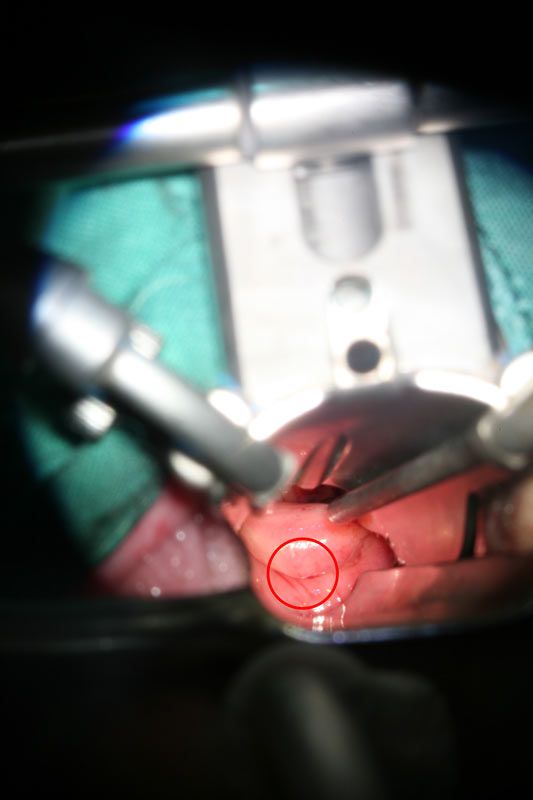

Abbildung: Blick auf den Eingang in ein Divertikel (Kreis)